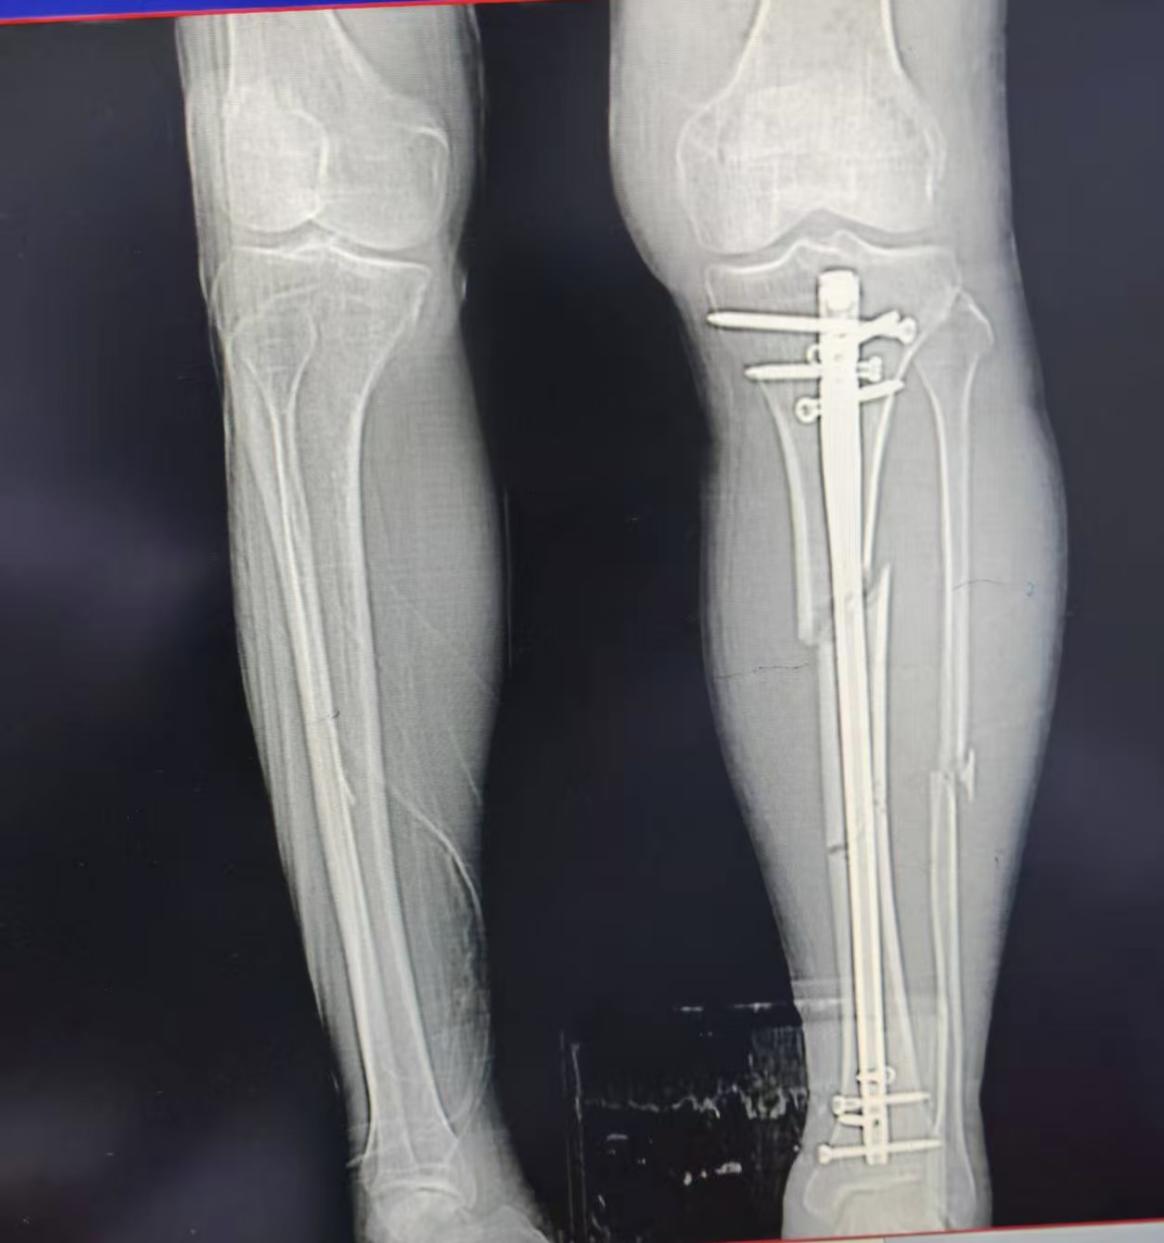

【医疗技术】微创精准“接骨” 小切口解决大难题——玉林市红十字会医院成功实施高难度胫骨多段骨折手术